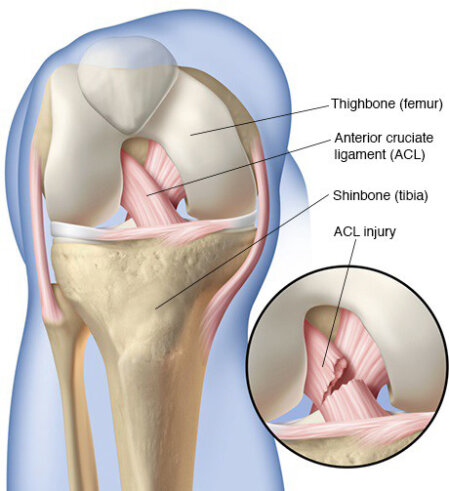

Cos'è il legamento crociato craniale?

Il legamento crociato craniale nei cani è lo stesso del legamento crociato anteriore negli esseri umani. È una fascia di tessuto fibroso resistente che collega il femore alla tibia, impedendo alla tibia di spostarsi in avanti rispetto al femore. Contribuisce inoltre a impedire l'eccessiva estensione o rotazione dell'articolazione del ginocchio.

I traumi al legamento negli esseri umani sono comuni e il danno si verifica più frequentemente durante qualche forma di attività sportiva. La natura della lesione del legamento crociato craniale è molto diversa nei cani. Invece di rompersi improvvisamente a causa di un trauma eccessivo, il legamento di solito degenera lentamente nel tempo, un po' come una corda che si sfilaccia. Questa importante differenza è la ragione principale per cui le opzioni terapeutiche raccomandate per la lesione del legamento crociato nei cani sono così diverse da quelle raccomandate per gli esseri umani.